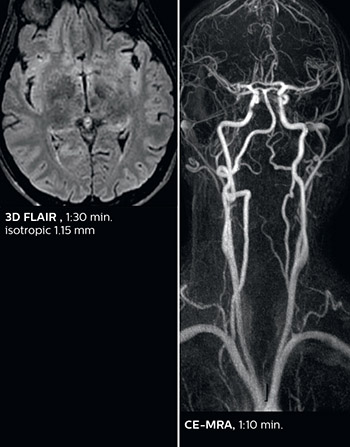

According to Dr. Savatovsky, Ingenia Elition has an impact in virtually all examinations. “We can either make the scanning faster compared to our older Ingenia 3.0T, or we save enough time so that we can add sequences we wouldn’t perform otherwise, or increase resolution. So, I think it has benefits for most of our patients.” “Some routine exams that we use every day have been shortened since we started using Elition. For example, we now use mostly a comprehensive stroke protocol (high b-value diffusion, fast 3D FLAIR, TOF, supra-aortic vessels angiography, SWIp, T1 post gad) that lasts 10 to 11 minutes, but our fast stroke protocol takes only 7 minutes. Our routine IAC needs about 10 minutes scan time and our comprehensive brain MS examination requires no longer than 13 minutes of scan time. Our ability to reduce acquisition times of most sequences helps to shorten total examination times, which in turn helps us to increase the number of patients we scan per day. “The main breakthrough for us was that Compressed SENSE and Multiband SENSE have allowed us to accelerate our examinations. Alternatively, we can invest the time gained in obtaining higher spatial resolution to see more details, or we can add additional sequences,” says Dr. Savatovsky. “That’s a big improvement from what we did before.”

This is an example of acute ischemic stroke with distal occlusion of the right posterior cerebral artery. Note the improved visibility of the ischemic territory on the diffusion weighted image with high b-value. The 3D FLAIR shows a distal PCA occlusion. The fast SWIp depicts the thrombus on the isolated second echo image. The total scan time (including SmartBrain, preparations and a fast 3D T1w TSE Gd) is 8:00 minutes.